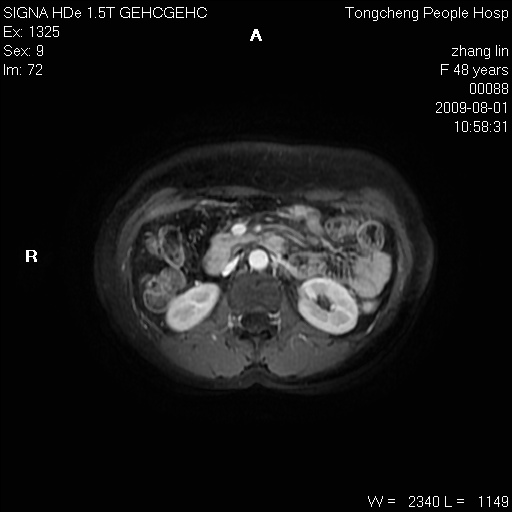

女,48岁。健康体检,彩超发现右肾占位性病变。平素健康。

临床诊断:右肾占位性病变,性质待定(囊肿?肿瘤?)。

上中腹部mr平扫+增强扫描,图像如下:

右肾上极见一类圆形病灶,t1wi呈等信号t2wi呈等高混杂信号,三期增强无强化,边界清---考虑囊肿出血。

同反相位均表现为等信号,病变无强化,考虑含蛋白的囊肿可能,弥散加权相或许有些帮助,

慢性胆囊炎